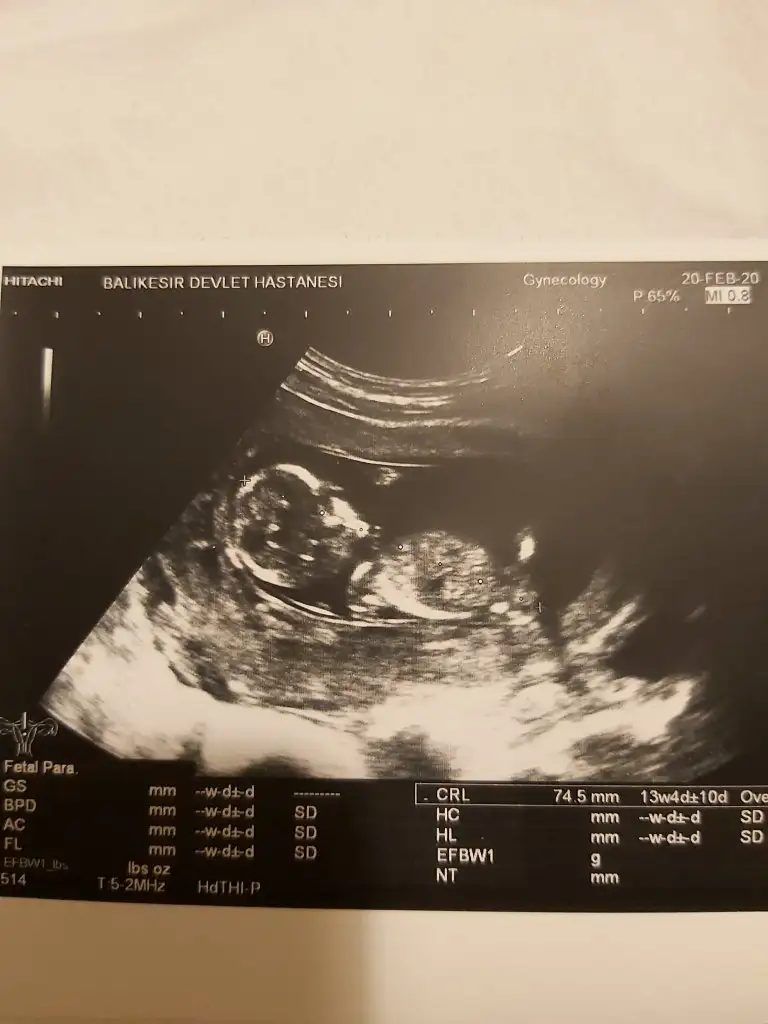

14. Haftada erkeğe benzettim demişti doktorum bugün ki farklı doktor da erkek gözüküyor dedi bklm hayırlısı cnmYaa tahminde bulundumu kızmı dedi kafa şekline göre tahminde bulundum şu an

Dogrudur canım kafa şekli pek tutmuyor14. Haftada erkeğe benzettim demişti doktorum bugün ki farklı doktor da erkek gözüküyor dedi bklm hayırlısı cnm ☺ Rabbim sağlıkla nasıp etsin de en önemlisi o tabi teşekkür ederim cevapladigin için yine de